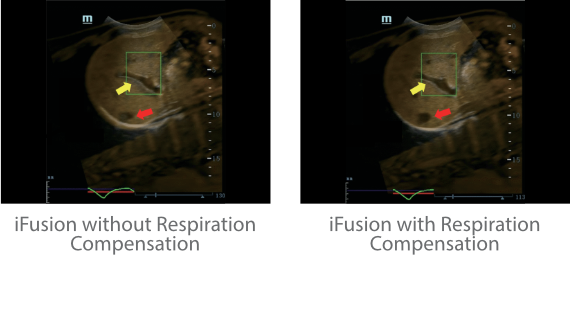

Since the company was founded, Mindray has been continuously exploring new ways to improve diagnostic confidence. Powered by the most revolutionary ZONE Sonography? Technology, Resona 7ŌĆÖs new ZST+ platform brings ultrasound image quality to a higher level by zone acquisition and channel data processing.

As well as the premium level image quality, Resona 7 also enhances clinical research capabilities with the revolutionary V Flow for vascular hemodynamic evaluation, and the most intelligent plane acquisition from 3D datasets for fetal CNS diagnosis. Combining the most intuitive gesture-based multi-touch operation and all the essential clinical features, Resona 7 is truly leading new waves in ultrasound innovation.